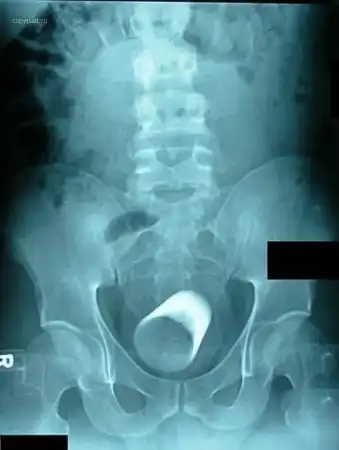

Пациент со стеклянной цилиндрической мензуркой в анусе. На уроках химии такого

не проходили